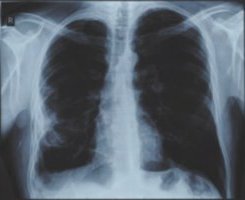

![]() Рис. 3 |

В феврале 2016 был сделан контрольный снимок (рис. 3). Результат был поразительным, от опухоли не осталось и следа, осталась только соединительная ткань на стенке легкого, на снимке она видна как еле заметная пелена.